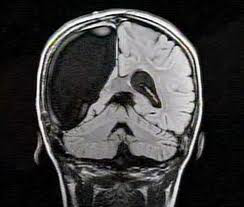

这是一张人体颅骨X光片▲,但左侧大脑却是完全空掉的。

这个孩子在刚出生时被诊断为重症癫痫,当时医生诊断他活不过两三岁,但更不幸的是,当他一岁多时,他的左侧大脑出现了无菌感染,并且开始萎缩,医生在征求家长同意后,切除了他整个左侧大脑。

在做完手术后,他竟顺利活过了医生给他判定的死亡的期限。不仅如此,他还在特殊学校顺利渡过了幼儿园与小学阶段。家长还发现,孩子其实除了数学不好,其他成绩还是不错的。所以家长又去求证专家,想知道孩子有没有可能上普通学校。

经过专家一系列的检查与测试,发现孩子数学成绩不好并不是因为缺失了左侧半球,而是他的工作记忆容量空间太小。普通人的工作记忆容量大概在5-9的范围内,而他的工作记忆容量空间只有3左右。

由于容量过小,所以他在进行相对复杂的数学运算时,会遗忘掉前面的运算信息,导致他计算到最后时无法得出正确结论。

但工作记忆容量是可以通过针对性训练进行有限扩容的。所以专家就为他设计了一系列针对性的扩容训练。

经过训练后,他的数学成绩有了大幅提升,更是顺利进入了普通中学学习,虽然成绩无法与“学霸”相提并论,但跟上普通中学生的学习进度是没问题的。

现在这个孩子已经成年了,正常地结婚、生子,像多数普通人那样完成着自己所担任的社会角色任务。很难想象,他只用了一半的大脑代偿了普通人完整的全脑所需要完成的任务。